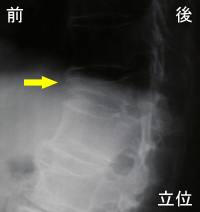

偽関節

場合によっては、骨折部がくっつかず

不安定な状態(偽関節)になることもあ

ります。右の写真では矢印の部分が偽

関節です。立位では臥位に比べて椎体

の前方が潰れて見えます。